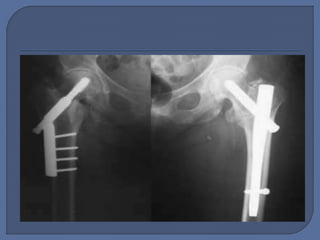

 Planning: • Nailor Screw? • Nail or screw properties  Execution: • Open • Reduce • Fix - position • Close  Tip 1: Use the Tip-to-Apex Distance  Tip 8: Avoid Varus Angulation of the Proximal Fragment—Use the Relationship Between the Tip of the Trochanter and the Center of the Femoral Head

• #30 Varus angulation of the proximal fragment increases the lever arm on the fixation since it makes the femoral neck more horizontal and therefore functionally longer when body weight is applied. This also results in the femoral head fixation being placed more superiorly in the head than is ideal and increases the risk of the device cutting out of the femoral head. It can be difficult to determine the appropriate femoral neck-shaft angle in a patient with an intertrochanteric fracture. When using an intramedullary nail for fixation of an intertrochanteric fracture, most surgeons choose a nail with a 130 neck-shaft configuration (Figs. 13 and 14). It is important to know the neckshaft angle of the device that is being used. One way to assess varus or valgus position during surgery is to look at the relationship between the tip of the greater trochanter and the center of the femoral head. These two points should be coplanar. If the center of the femoral head is distal to the tip of the greater trochanter, the reduction is in varus. If the center of the head is proximal to the greater trochanter, the reduction is in valgus. Preoperative plain radiographs of the uninjured hip can be used to assess the patient’s normal neck-shaft angle as the two sides are normally symmetric. Varus and high lag-screw placement are associated with an increased frequency of failure of fixation with an intramedullary nail and sliding hip screw20,21. (Fig. 13 A well-aligned fracture. Note the central position of the lag screw in the femoral head. Fig. 14 Radiograph showing the relationship between the tip of the greater trochanter and the center of the femoral head. Normally, this relationship is coplanar. Here, the proximal fragment is in varus, the starting point is lateral, and the screw is high in the head.)